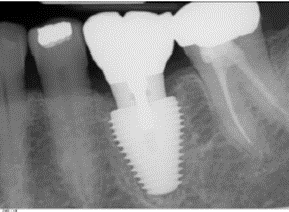

This patient had a crowned first molar tooth with area of infection (the dark area between the roots) (A). This tooth was removed, and dental implant (titanium screw) was placed immediately follow the extraction. Three month later, the restorative specialist placed a crown attached to the implant (B).

B